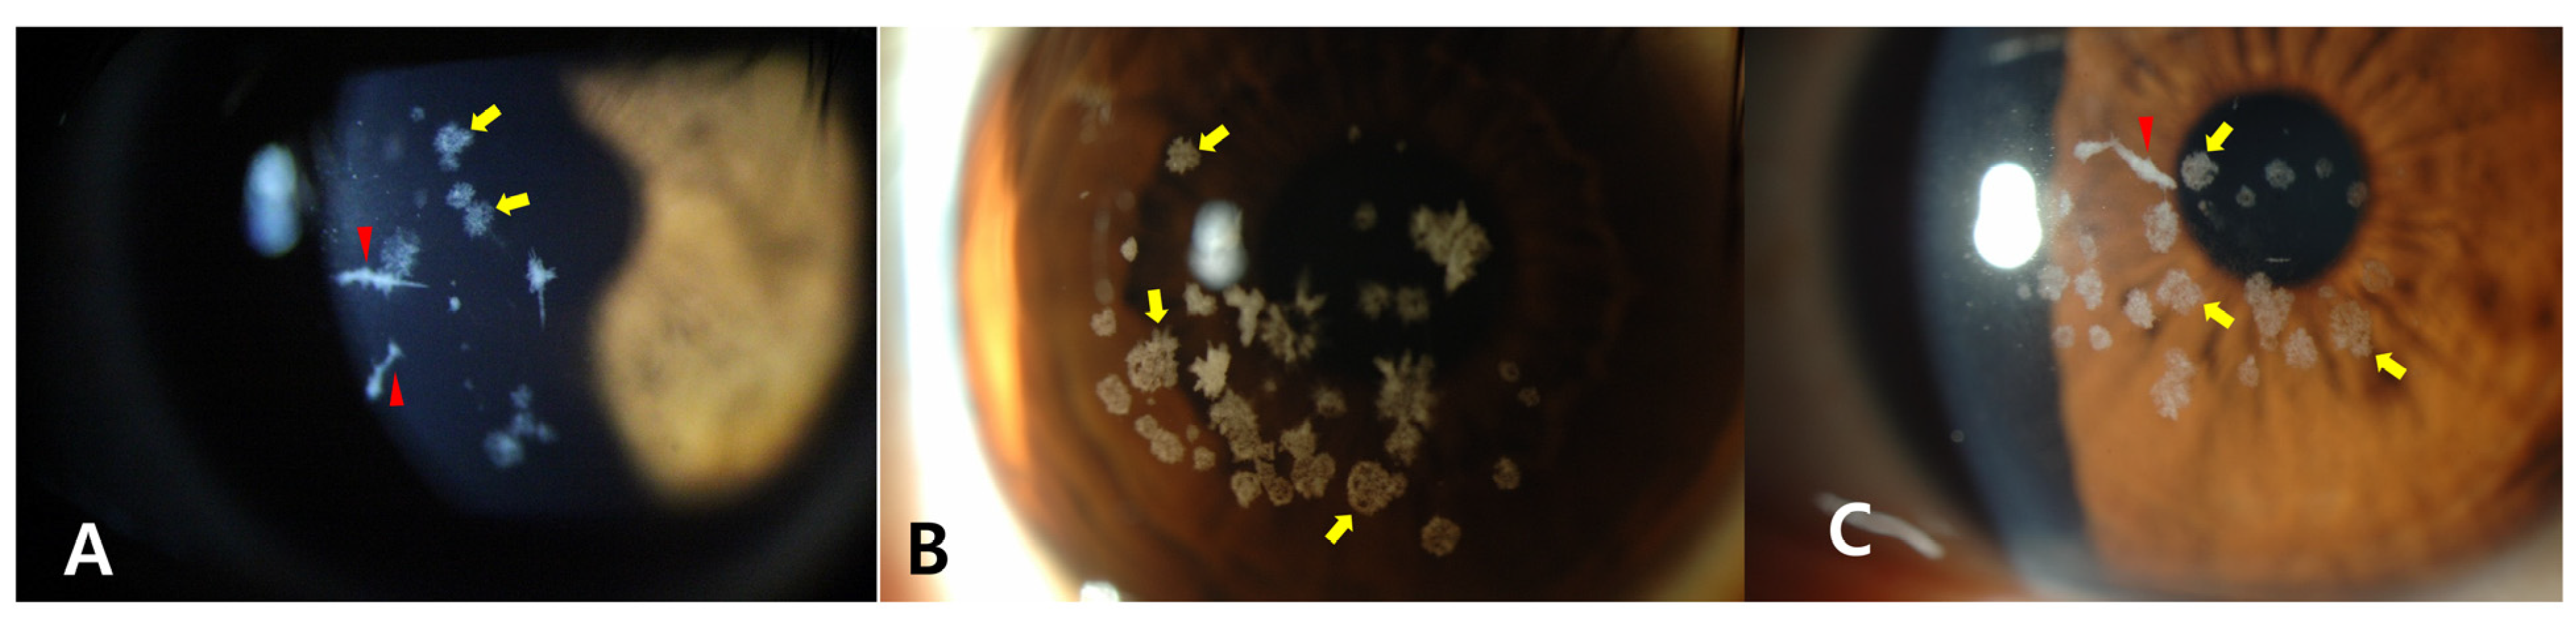

2. Case Presentation

2.1. Clinical Analysis